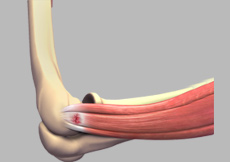

Tennis Elbow

Tennis elbow is a common name for the elbow condition lateral epicondylitis. It is an overuse injury that causes inflammation and microtears of the tendons that attach to the lateral epicondyle.